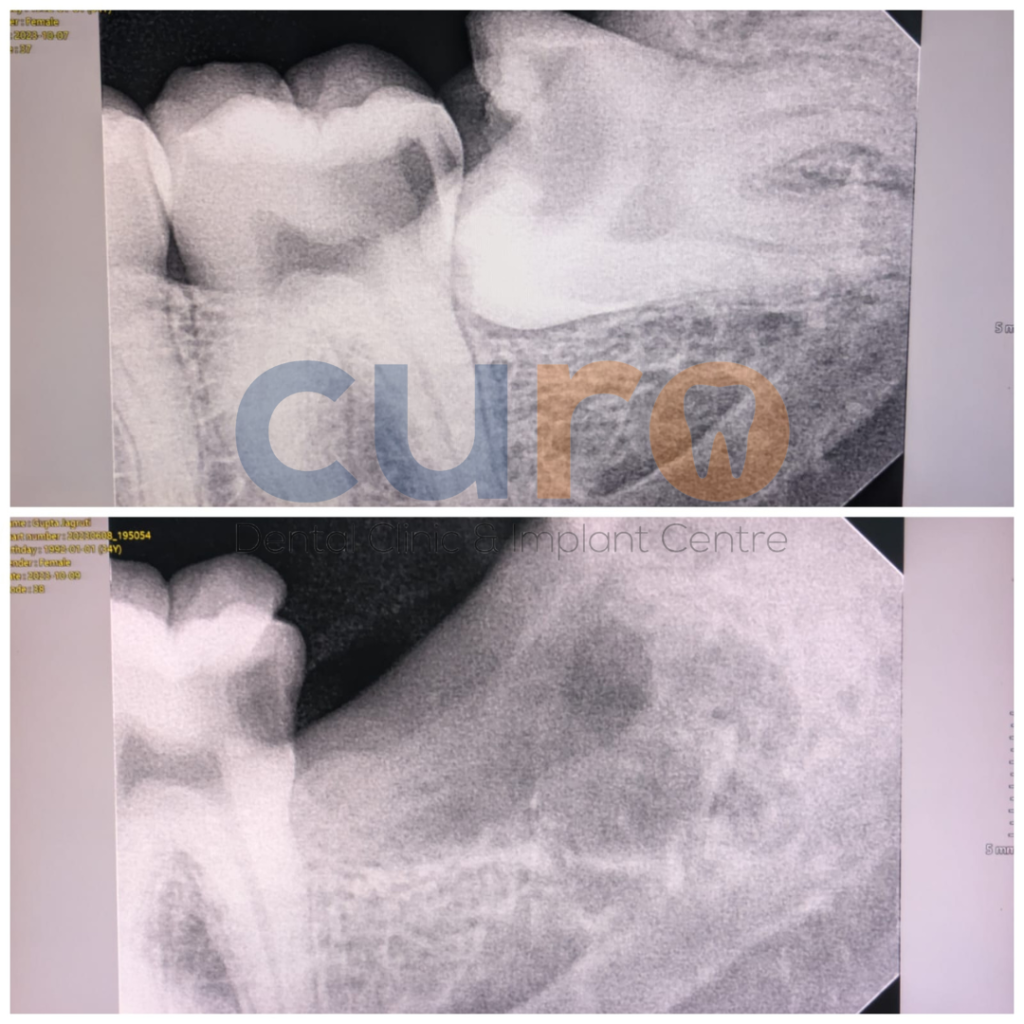

Surgical Wisdom Tooth Removal

Advanced surgical extraction for impacted or partially erupted wisdom teeth.

Impacted Tooth Removal

Treatment for teeth trapped inside gums or jawbone.